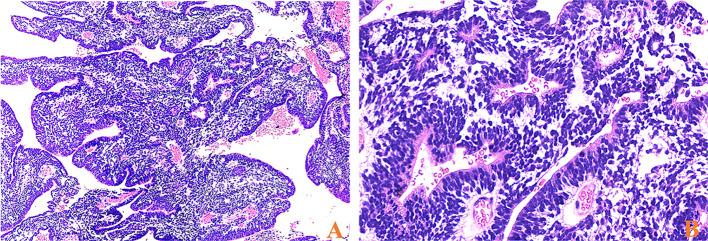

Embryonal tumors with multilayered rosettes (ETMRs) are a histologically heterogeneous entity and gather embryonal tumors with abundant neuropil and true rosettes (ETANTRs), ependymoblastoma, and medulloepithelioma. ETMRs are highly aggressive and associated with poorer clinical courses. However, cases of this entity are rare, and advances in molecular genetics and therapy are minor. The purpose of our study was to retrospectively analyze the clinical, pathological features, and prognostic factors of ETMRs.

Among 17 cases, 16 were ETANTRs, and one was medulloepithelioma. Morphologically, tumor cells of ETANTRs could transform into anaplasia and lose the biphasic architecture during tumor progression. Immunohistochemistry of LIN28A revealed positive expression in 17 cases, and the expression of LIN28A was more intense and diffuse in the recurrent lesions than in primaries. The increased copy numbers were detected in the primary tumor and recurrence of patient 8. Moreover, the incidence of metastatic disease was 100% in patients aged > 4 years and 18% in the younger group. For patients receiving chemotherapy, the median overall survival time was 7.4 months, while that of those who didn't receive it was 1.2 months. Nevertheless, surgical approaches, radiotherapy, age at presentation, gender, tumor location, and metastatic status were not associated with independent prognosis.

17例中,16例为ETANTRs,1例为髓上皮瘤。形态学上,ETANTRs的肿瘤细胞在肿瘤进展过程中可转变为间变并失去双相结构。LIN28A免疫组化显示17例均呈阳性表达,且LIN28A在复发病变中的表达比原发病变更强烈和弥漫。在患者8的原发肿瘤和复发灶中检测到拷贝数增加。此外,年龄>4岁患者的转移率为100%,较年轻组为18%。接受化疗的患者中位总生存时间为7.4个月,未接受化疗的患者为1.2个月。然而,手术方式、放疗、就诊年龄、性别、肿瘤部位和转移状态与独立预后无关。